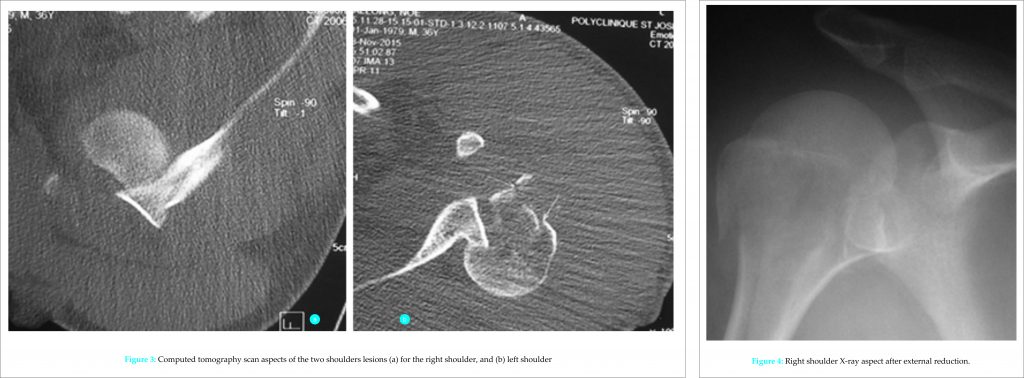

The CT scan has detailed bone lesions (Fig. 3). There was no notion of falling during or after these convulsions. The following day, the traumatic lesions were reduced by external maneuvers for the right shoulder (Fig. 4) and open reduction and internal fixation by anatomical plate of left shoulder lesions through a transdeltoid longitudinal approach. The two shoulders were immobilized complementarily by removable splints arm to the body. In the immediate aftermath of surgery, he presented episodes of agitation which led to the dismantling of the left shoulder internal fixation (Fig. 5). The improvement of its neurological state and of the biological markers toward the 15th day allowed a reprise of the left shoulder with contribution of graft and a fixation of the major tubercle on the right.

At the request of his entourage, he was evacuated to the North Country where an ablation of the left shoulder material and stabilization by locked plate were carried out (Fig. 6). The sequelae were marked by the occurrence of an osteomyelitis with osteolysis of the entire upper right humerus extremity (Fig. 7). It will require an inverted prosthesis.